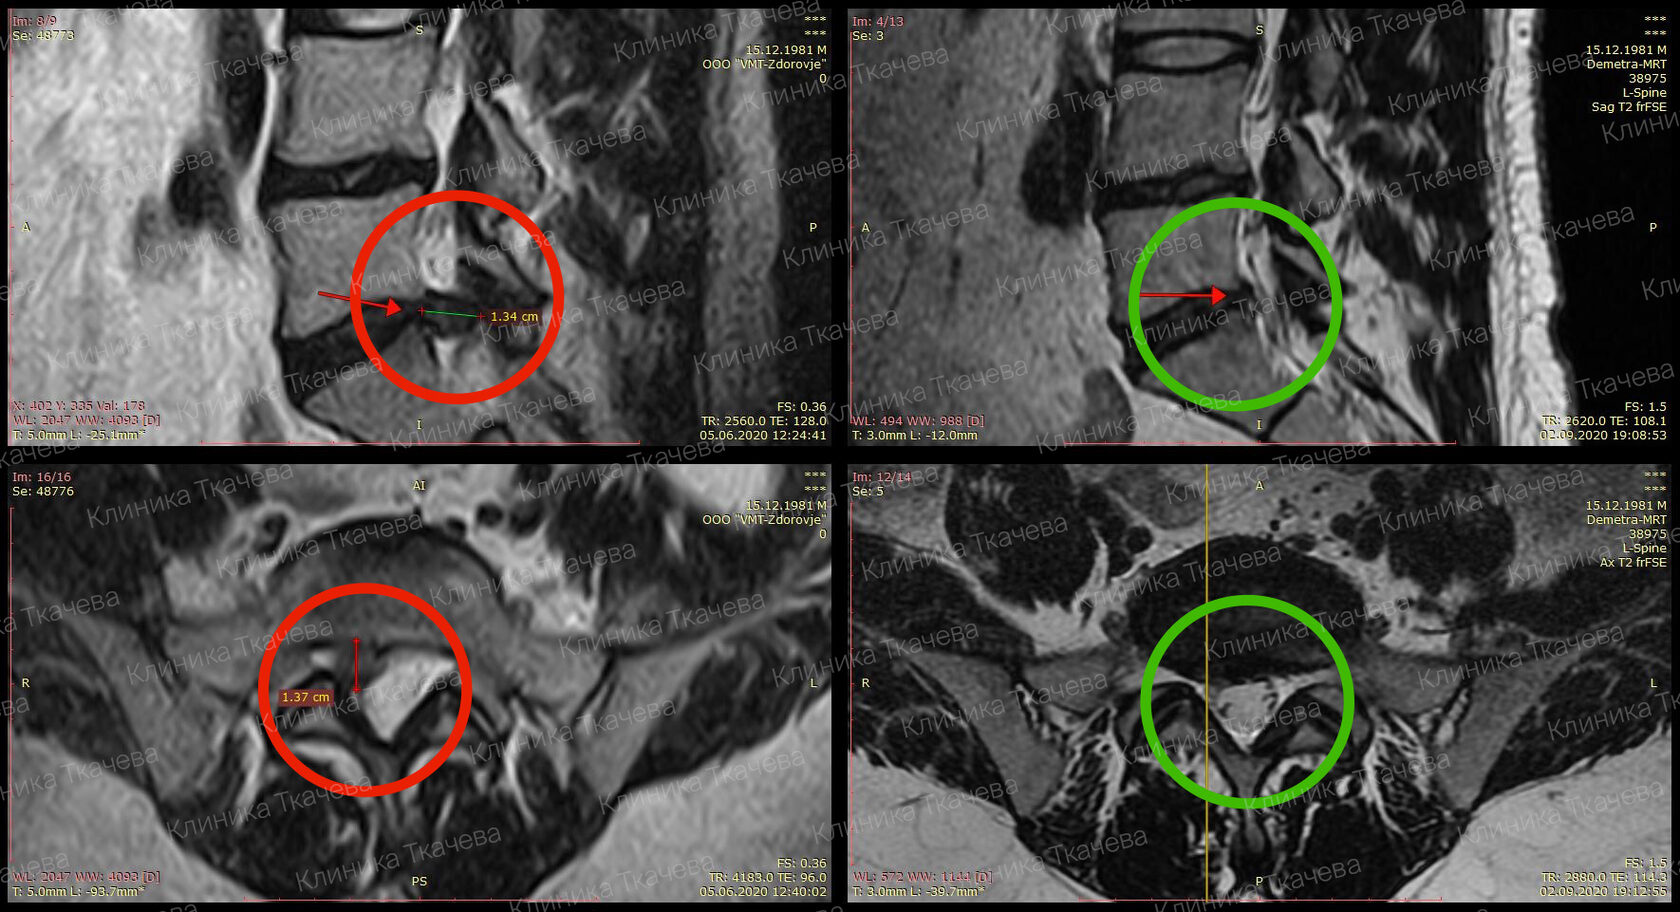

Грыжа Диска L5 S1 Фото

Грыжа Диска L5 S1 Фото 108 фотографий